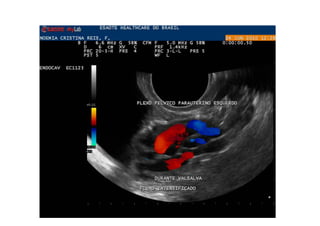

Refluxo  de  veia  Gonadal  com  formação   varicosa  ao  lado  do  ovário

Comment  établir  le  diagnos=que  ?   1.  Par   la   symptomatologie,   en   par8culier   la   douleur  et  la  lourdeur  dans  le  bassin  avec  une   aggrava8on   pendant   la   menstrua8on,   mais   aussi   la   dysménorrhée,   la   dyspareunie,   la   cons8pa8on  et  les  douleurs  lombaires.   2.  Par   la   présence   de   varices   dans   la   région   postérieure   et   latérale   des   cuisses,   dans   les   fessiers  et  les  par=es  génitales.   3.  À   l’aide   d’un   écho-­‐doppler   transvaginal   et   abdominal.

En  rappel:  avant  traitement   Phlébographie  et  echographie  transvaginale   (slide  suivant)

CONCLUSION  :   • La   phlébographie   et   l’embolisa=on   ont   amélioré   significa=vement   la   situa=on   phlébologique   et   clinique   :   dispari8on   de   la   douleur   pelvienne,   de   la   sensa8on   de   pesanteur  dans  les  membres  inférieurs  et  de   la  cons8pa8on  intes8nale   •  Aucune   complica=on   sérieuse   n’a   été   constatée   Kennedy-­‐gp@uol.com.br